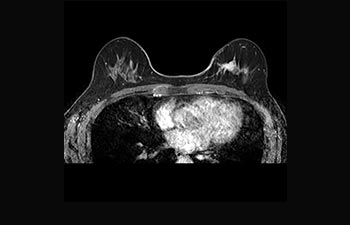

Enhanced diagnostic confidence in neuro oncology

Find the right clinical applications for your needs